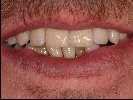

- Individuell charakterisierte Prothesenzähne und Basen sind im Mund des Patienten von einer natürlichen Situation kaum zu unterscheiden.